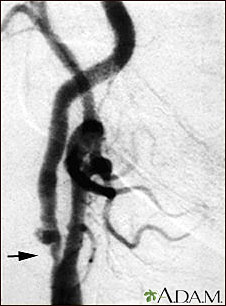

Carotid stenosis, x-ray of the right artery

This is an angiogram of the right carotid artery showing a severe narrowing (stenosis) of the internal carotid artery just past the carotid fork. There is enlargement of the artery or ulceration in the area after the stenosis in this close-up film. Note the narrowed segment toward the bottom of the picture.